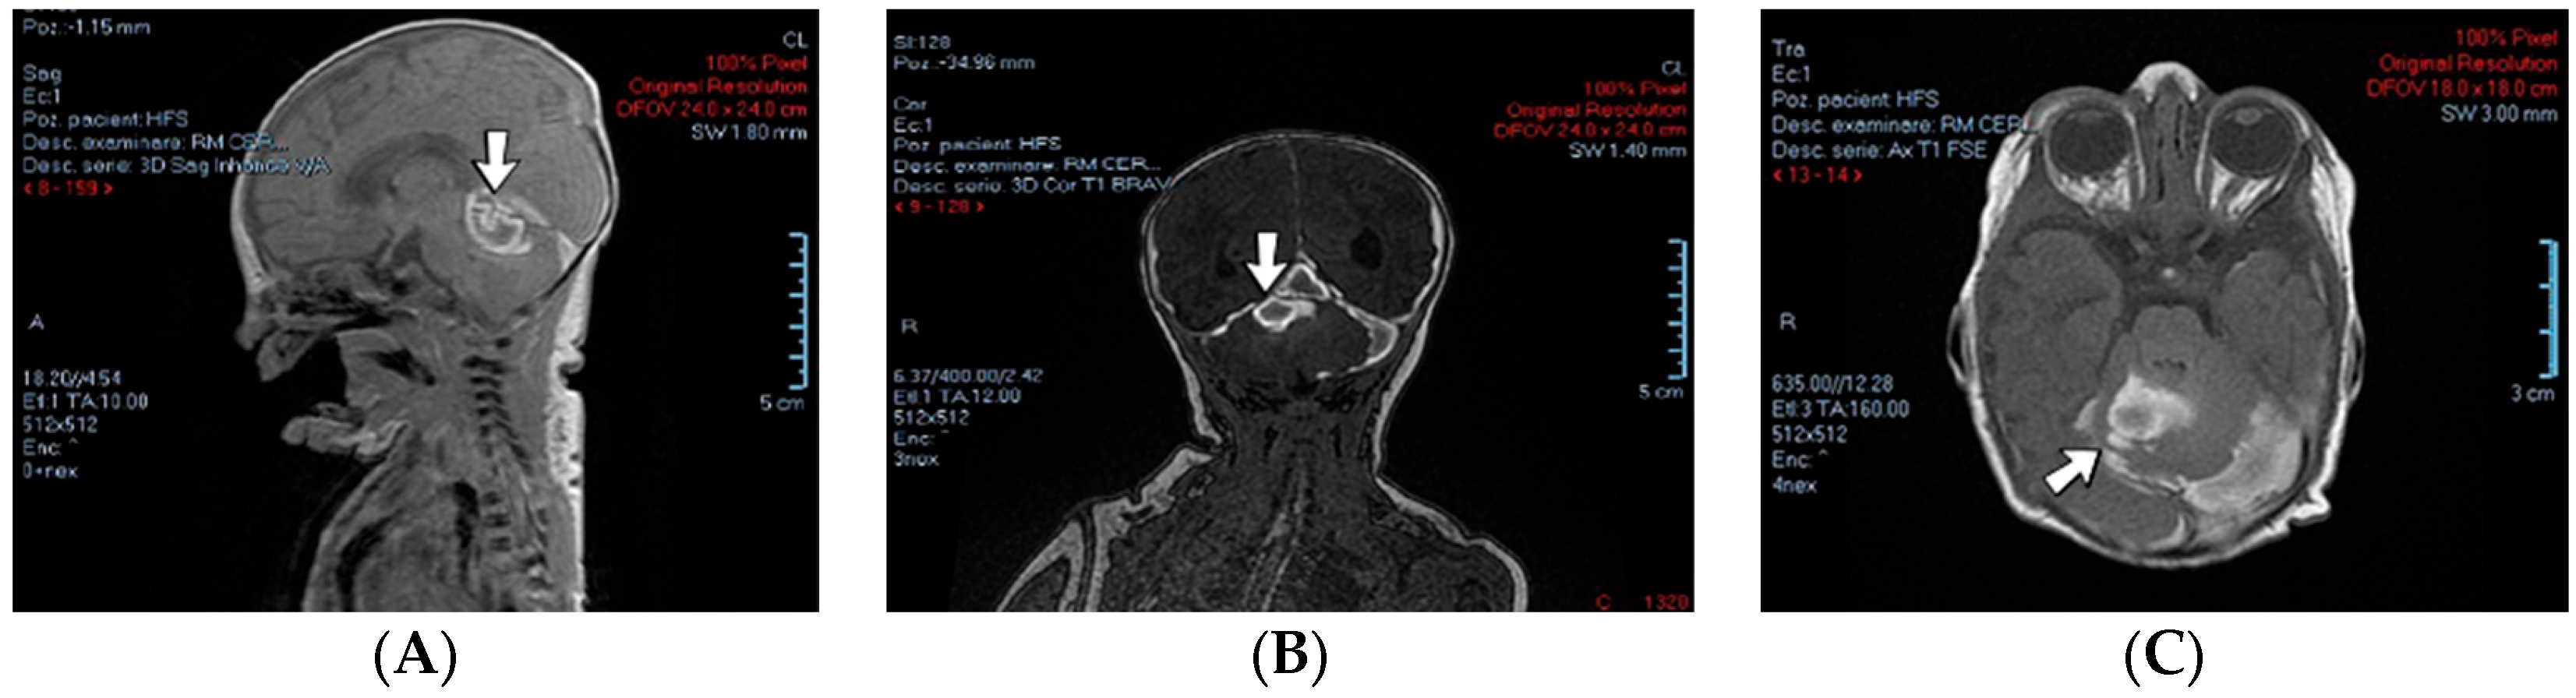

A 4-day-old female neonate (40 weeks, 3.10 kg) presented signs of increased intracranial pressure: projectile vomiting, bulging anterior fontanelle, and spasticity. The patient had previously developed seizures at 8 h of life, treated with phenobarbital. The first ultrasound of the brain performed at birth was normal; the second one performed at 3 days of life showed hydrocephalus of the lateral ventricles. A brain CT scan performed at 3 days of life identified right pericerebellar hemorrhage in the posterior cranial fossa, causing stenosis of the Sylvius aqueduct, hydrocephalus, and subarachnoid hemorrhage of the right temporal lobe, tentorium cerebelli, quadrigeminal, and ambiens cisterns of the brain (Figure 6). The laboratory findings from birth and 3 days of life showed leukocytosis.

Figure 6.

Case no. 15. Posterior cranial fossa hemorrhage on brain MRI—sagittal (A), frontal (B), and transverse (C) views.

The admission laboratory findings showed elevated procalcitonin. Two RT-PCR tests for SARS-CoV-2 infection were performed with negative results due to a positive maternal infection before birth. Later, a brain MRI performed at 7 days of life showed thrombosis of the right transverse and sigmoid cerebral venous sinuses and mild hydrocephalus of the lateral ventricles. A suspicion of right internal jugular vein thrombosis and elevated D-dimer tests led to the initiation of treatment with enoxaparin.

Genetic testing confirmed inherited thrombophilia, with a positive MTHFR C677T homozygous gene mutation and Protein C deficiency. Normal homocysteine and PAI-1 levels were detected. There was a positive maternal history of three miscarriages and oligohydramnios during pregnancy.